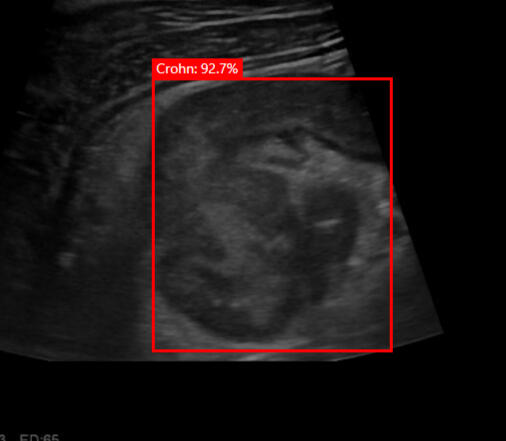

AI for ultrasound detection

Hekia is involved with Professor Fumery (CHU-Amiens-Picardie/UPJV) in the ECHIA-IBD1 project for real-time detection of Crohn's disease. The aim of this project is to speed up diagnosis by non-specialists in IBD ultrasound, make digestive tract ultrasound more accessible for monitoring Crohn's disease and UC activity, and improve patient outcomes.

Medical project in progress: RHU I-DEAL

As part of France 2030, Hekia, with its embedded artificial intelligence solution, is taking part in the project headed by Professor Laurent Peyrin-Biroulet. The RHU I-DEAL focuses on the development of innovative tools for remote monitoring and precision imaging, aimed at the early management of Crohn's disease. The aim of this project is to meet the needs of Crohn's patients by enabling earlier intervention and promoting a faster return to normal life.